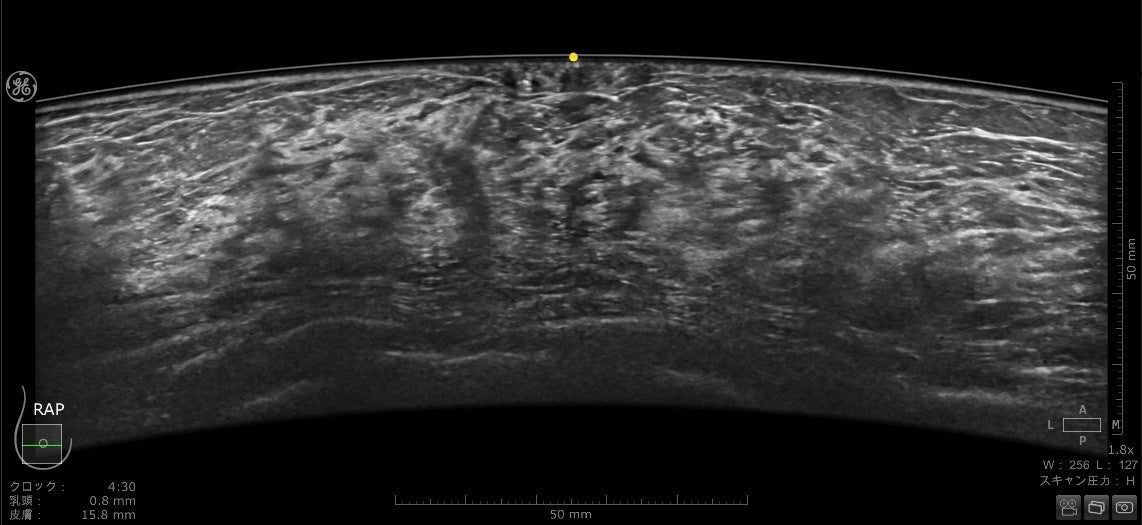

2. より美しい画像

乳房にあてるプローブは、よりフィットするように設計され、周波数帯域も広がったことで空間分解能とコントラスト分解能が向上しています。全ピクセルにフォーカスがあたる信号処理、乳頭直下が見えやすくなる画像処理は刷新され、より均一性の高い画像を提供します。